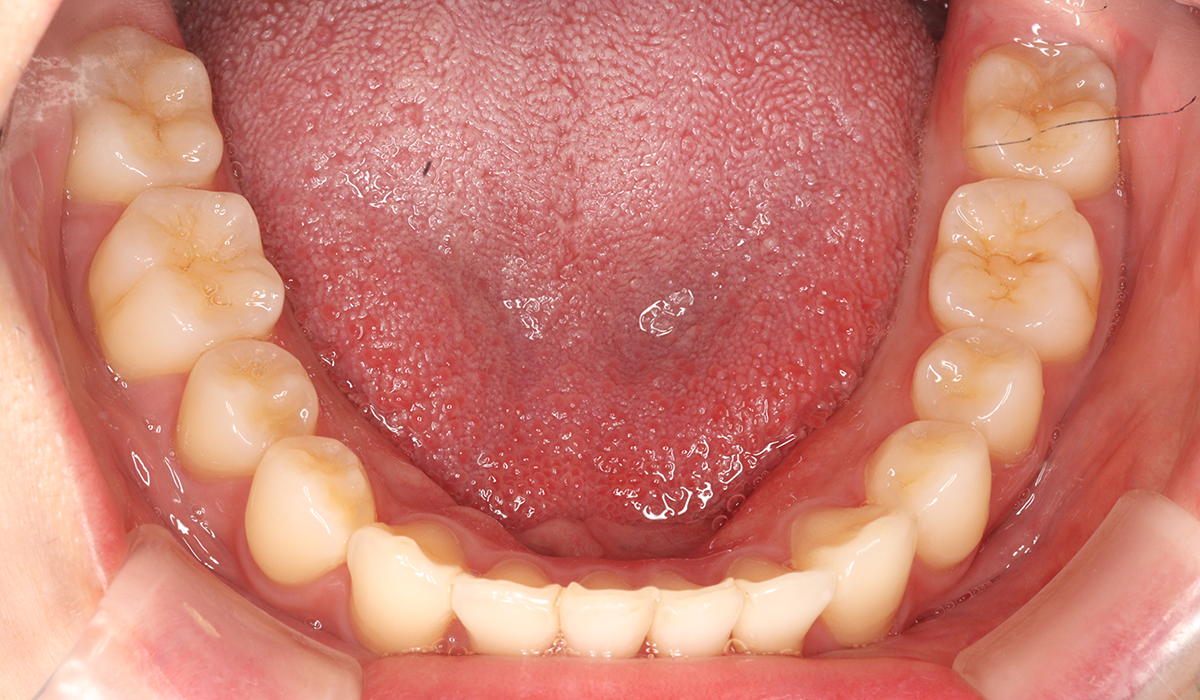

下顎

BK終了時